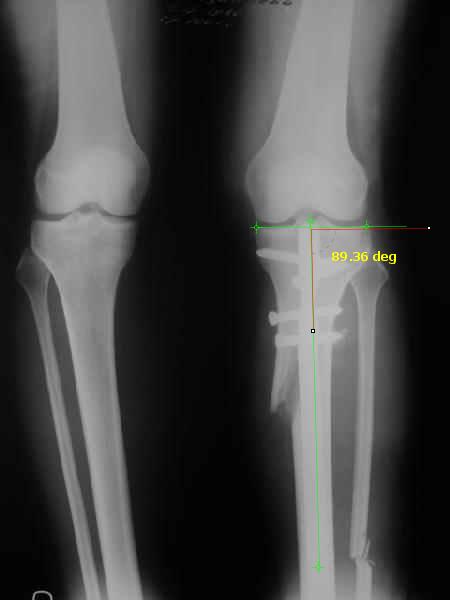

Снимки в приложении - фас сравнительный с неоперированной ногой. Жду критики.

The analysis in the attached images is direct, just using the tools.

Tibial tilt is perhaps more than you want but the tibial correction is to 90 (very slight over

correction.

Measurements took 4 mins